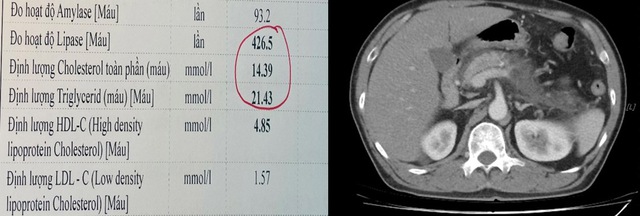

Theo bác sĩ Tô Hoàng Dương - Phó Trưởng khoa Hồi sức tích cực và chống độc, Bệnh viện Hữu Nghị, đây là một trường hợp đã có tiền sử viêm tụy cấp cách đây 02 năm, đái tháo đường và rối loạn mỡ máu. Bệnh nhân nhập viện tại khoa Cấp cứu trong tình trạng đau bụng dữ dội vùng thượng vị, xét nghiệm có tình trạng men tụy và mỡ máu tăng rất cao, gấp khoảng 12 lần giá trị cho phép (Cholesterol là 14.3 mmol/L và Triglyceride là 21.43 mmol/L). Trên hình ảnh phim chụp cắt lớp vi tính ổ bụng cho thấy tụy đã bị tổn thương nặng, thâm nhiễm kèm tụ dịch xung quanh.

Kết quả xét nghiệm mỡ máu tăng rất cao (trái) và hình ảnh tổn thương viêm tụy cấp mức độ nặng trên phim CT ổ bụng của bệnh nhân (phải).